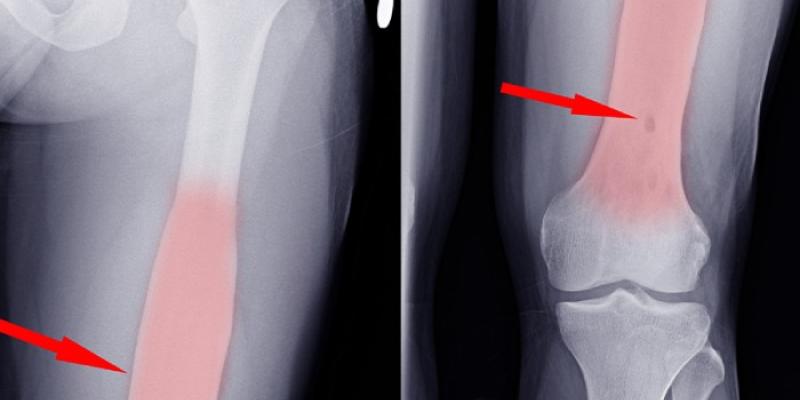

La enfermedad que padece el presidente, conocida técnicamente como osteomielitis, es una infección que afecta tanto al tejido óseo como a la médula. En este caso particular, la infección se ha localizado en los huesos de la pelvis (ilion, isquion o pubis), una variante especialmente rara y compleja. El origen del proceso ha sido identificado como la bacteria Streptococcus dysgalactiae, aunque los médicos recuerdan que, en términos generales, la causa más común de cualquier tipo de infección ósea suele ser el Staphylococcus aureus, una bacteria presente de forma natural en nuestra piel.

El riesgo de esta dolencia reside en su capacidad para pasar desapercibida en sus etapas iniciales. Al afectar a estructuras internas como el pubis, el dolor puede confundirse fácilmente con una lesión muscular o una dolencia articular común. Sin embargo, la osteomielitis demanda una intervención rápida; de lo contrario, la bacteria puede causar daños estructurales permanentes en el hueso o extenderse a tejidos adyacentes, complicando gravemente el pronóstico del paciente.